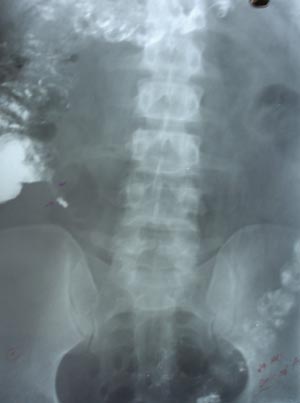

Barium visualizing appendix

Filling defect may be suggestive of appendicolith. There is high correlation of presence of appendicolith & appendicitis. But better way of imaging will be ultrasonography or CT, which can locate surrounding pathology with condition of caecum.